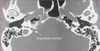

- Qual o nome dessa anormalidade osteomembranosa? - É possível realizar implante? - Qual a diferença dela para hipoplasia coclear?

- Aplasia coclear (ausência da cóclea, a partir de 5 semanas de gestação). - A aplasia coclear é rara, a cóclea não existe, o vestíbulo e canais semicirculares são anormais e na TC ocupam posição posterior ao conduto auditivo interno. NÃO POSSUI NERVO AUDITIVO. Não tem como fazer implante coclear, precisa ser implante de tronco encefálico. - Na hipoplasia coclear a cóclea já está presente, porém pouco desenvolvida (aproximadamente 6mm. Tem 4 subtipos, podendo ser de várias formas. Na imagem abaixo, hipoplasia coclear do tipo 1). O uso de implante coclear deve ser individualizado.